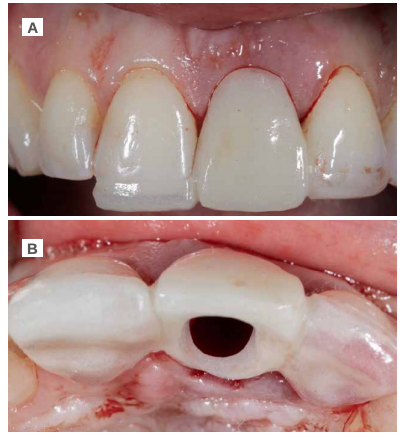

Caso clínico: Se presenta el caso de una paciente mujer de 32 años de edad, que acude por presentar una posible fractura radicular del incisivo central superior izquierdo (ICSI), acompañada de la aparición de un absceso periodontal en la región del fondo de vestíbulo de dicho diente. Tras llevar a cabo la exploración clínica y radiológica, se establece que el pronóstico del ICSI es desfavorable para llevar a cabo un tratamiento conservador del mismo. Tras la valoración de las características clínicas del caso presente, el plan de tratamiento se inclinó por la realización de la exodoncia del ICSI con la colocación simultánea de un IOI postextracción y la carga inmediata con una prótesis provisional del mismo.

Clinical case: We present the case of a 32-year-old female patient who presented with a possible root fracture of the upper left central incisor (ULCI), accompanied by the appearance of a periodontal abscess in the region of the bottom of the vestibule of said tooth. After carrying out the clinical and radiological examination, it is established that the ULCI prognosis is unfavourable for carrying out conservative treatment of the tooth. After assessing the clinical characteristics of the present case, the chosen treatment plan was to extract the ULCI with the simultaneous placement of a post-extraction osseointegrated implant (OII) and immediate loading of a provisional prosthesis on the implant.